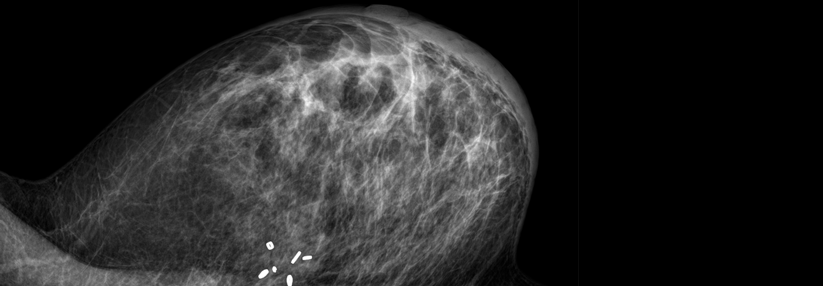

Frauen mit Brustkrebs-Gen möglichst wenig röntgen!

Bei Trägerinnen der BRCA-1- oder -2-Mutation erhöht jede Röntgenuntersuchung vor dem 30. Lebensjahr das Brustkrebsrisiko.